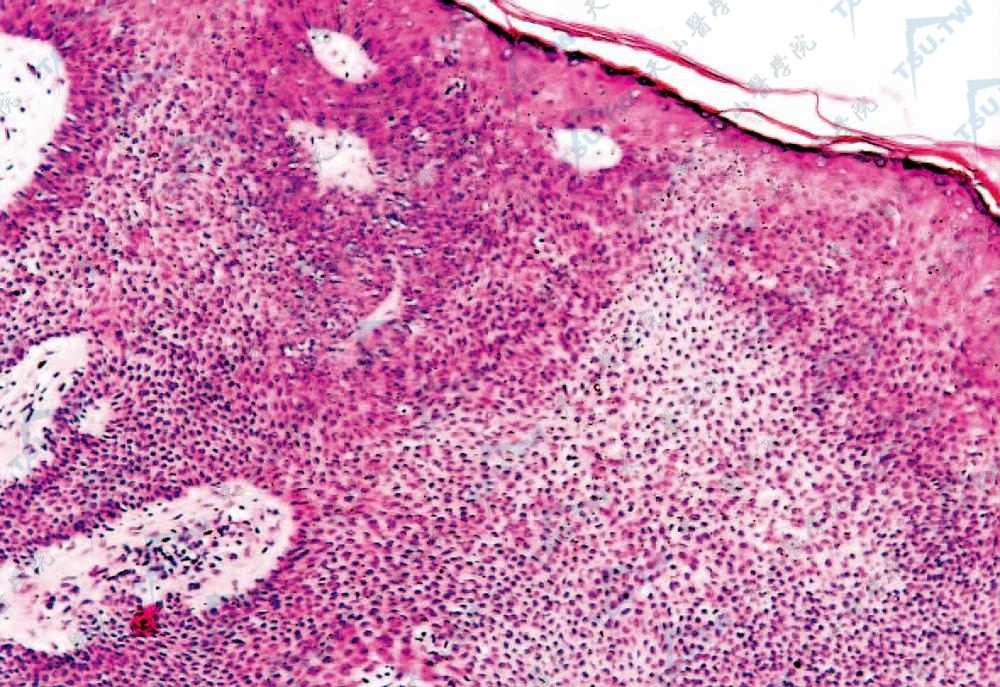

小汗腺汗孔癌 肿瘤位于表皮内,由基底样细胞和少数呈团块状分布的不典型嗜伊红鳞状细胞组成

小汗腺汗孔癌 周围基底样细胞体积较小,呈立方形,排列紧密,中央不典型嗜伊红鳞状细胞体积较大,核深染,有明显异型性